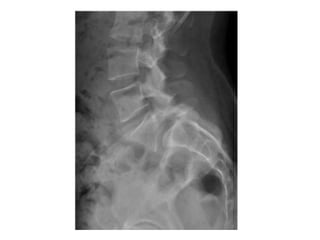

Rx

• Ap Laterales y oblicuas

• Grado de listesis (lateral)

Rx • Ap Lateralesy oblicuas • Grado de listesis (lateral) • Perritos de Lachapelle (Oblicua) 1. Hocico que es la apófisis transversa 2. Ojo, pedículo 3. Oreja, apófisis articular superior 4. Pata delantera, apófisis articular inferior 5. Rabo, lámina y apófisis articular superior del lado opuesto 6. Pata trasera, apófisis articular inferior lado opuesto 7. Cuerpo, lámina